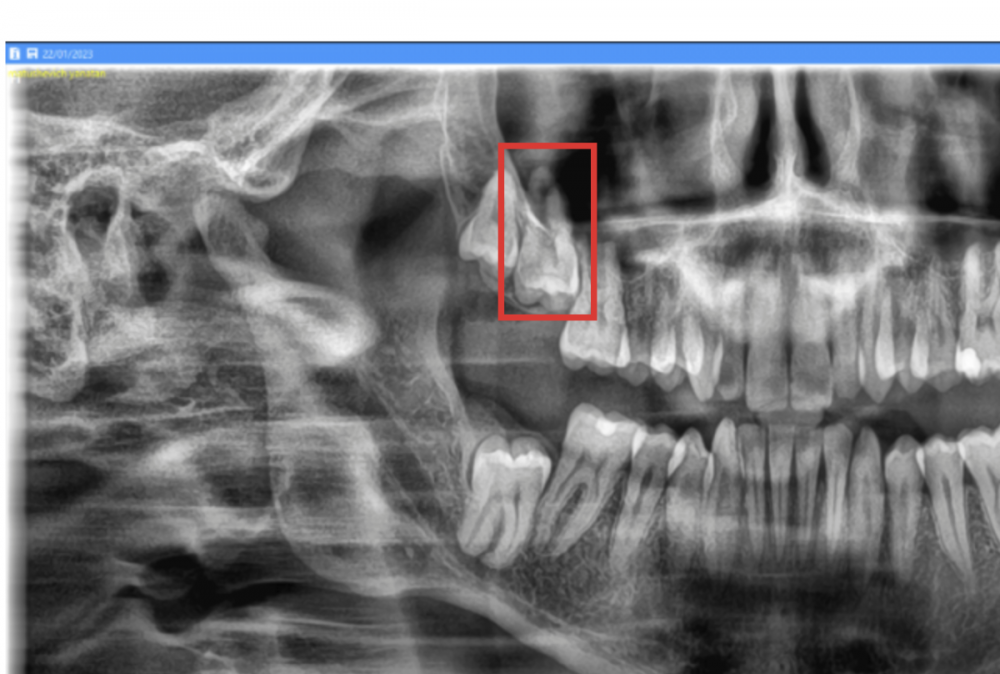

msp Опубликовано 4 мая, 2023 Автор Поделиться Опубликовано 4 мая, 2023 Всем привет, вопрос. Обведенный красным на снимке второй моляр - я правильно понимаю, что у него корень находится в синусе? Ссылка на комментарий

Doc Опубликовано 6 мая, 2023 Поделиться Опубликовано 6 мая, 2023 04.05.2023 в 19:22, msp сказал: Всем привет, вопрос. Обведенный красным на снимке второй моляр - я правильно понимаю, что у него корень находится в синусе? Вероятно, но не факт. На плоском снимке сложно определить как что расположено. Нужно делать КТ. 2 Ссылка на комментарий